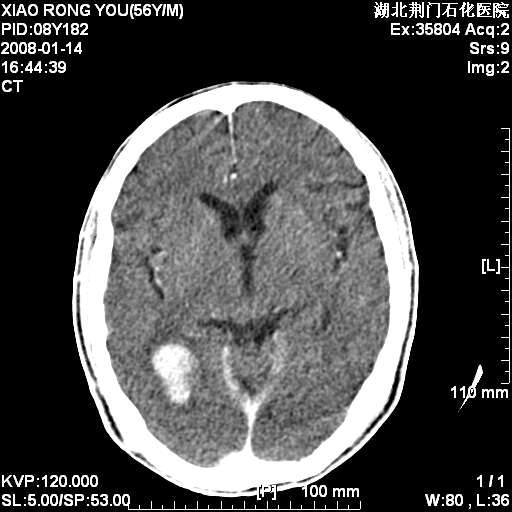

男性,68岁,多年肺结核病史。最近ct复查右肺有占位。

3天后增强

增强明显强化,转移?

如此血管样强化表现,转移瘤不好解释,考虑脑膜瘤或血管瘤

平扫无明显占位及水肿、增强扫描强化明显以血管瘤可能性大